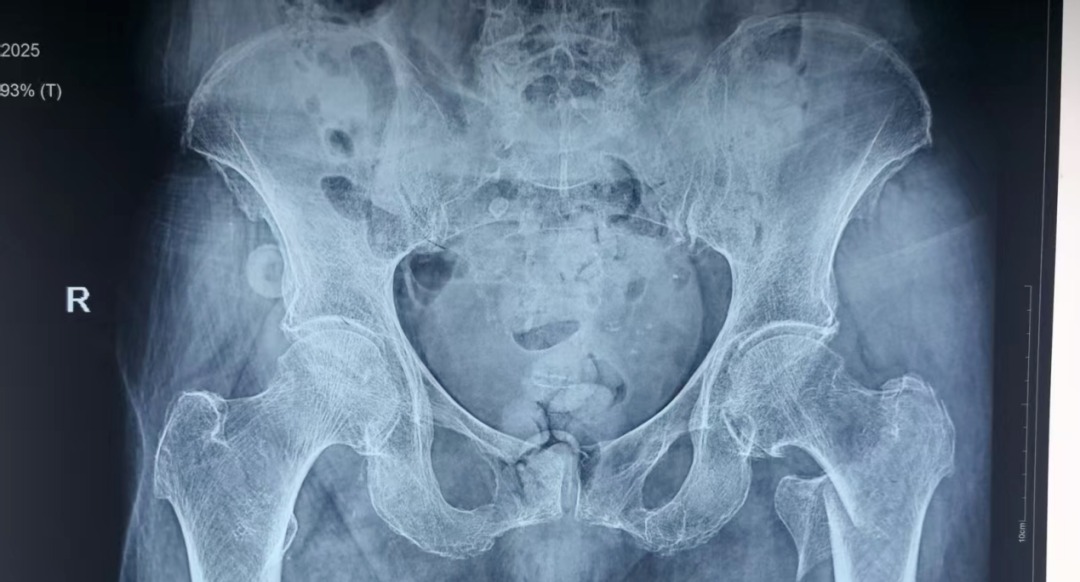

近日,患者李某某在即将迎来自己103岁生日时,不慎在家摔倒导致左髋关节疼痛伴活动受限,就诊于当地医院诊断为左侧股骨转子间骨折,因患者为超高龄老人,当地医院考虑手术风险大,建议转诊上级医院进行治疗。患者家属遂联系120转诊至东京热

为防止坠积性肺炎、褥疮、深静脉血栓等并发症发生,杨自权主任团队在患者入院后,积极完善术前准备,经过医务处的组织和血管外科、麻醉科、康复科等多学科的MDT合作,手术时间定于患者入院第三天。2022年,美国AAOS(美国骨科医师协会)指南强烈推荐老年股骨转子间骨折(稳定或不稳定)采用髓内钉内固定。因此,杨自权主任团队拟行股骨转子间骨折闭合复位髓内钉内固定微创手术。

手术当日,杨自权主任团队借助丰富的手术经验,术前在牵引床、G臂辅助下迅速给予患者闭合复位骨折断端,结合经典的“2-1-1”微创手术切口实施手术,手术过程顺利,G臂透视可见骨折复位满意,髓内钉位置满意。术后患者顺利出院,安返家中。